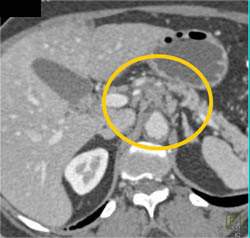

Superior Mesenteric Vein (SMV) Clot Due to Pancreatitis